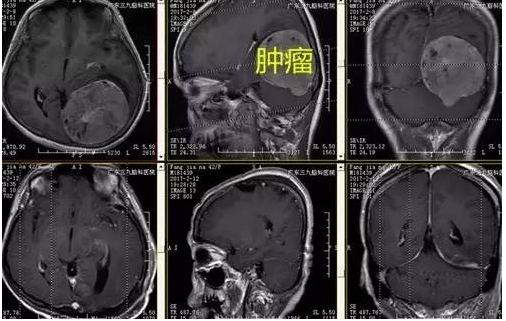

入院后完善相关术前检查, CTA显示肿瘤血供丰富,磁共振增强邻近脑组织稍扩大,显示肿瘤大小8.0cm*7.2cm*6.5cm,考虑到患者瘤体大,血管丰富,为保证病人的安全,科室专家讨论,选择择期全麻下行“小脑幕脑膜瘤切除术”,手术由神经外一科主任张良主刀完成,术程顺利,术后患者恢复良好,未见明确并发症,术后MR提示肿瘤切除,术后病理提示纤维细胞型脑膜瘤(WHO I级)。

↑手术前后MR对比

术前完善的影像学检查有利于更好地手术评估,制定翔实的手术方案,CTA及MRI为必不可少。本例患者CTA示肿瘤内血管丰富,邻近左侧大脑后动脉受压向右侧移位,MR呈长等T1长等T2异常信号影,增强后病变不均匀明显强化,局部向幕下呈结节状突出,范围约为8.0cm*7.2cm*6.5cm。MRV示:受肿瘤压迫,左侧横窦未见显示,上矢状窦后部变细,直窦显影浅淡;大脑表浅静脉增多。

手术切除程度及术后病理是影响患者预后和复发的两个重要因素。本例患者为跨小脑幕巨大脑膜瘤,术后MR提示肿瘤切除,术后患者恢复良好,未见手术并发症,术后病理为I级纤维细胞性脑膜瘤。小脑幕骑跨巨大脑膜瘤比较少见,对手术人路选择,术中显微手术技巧及神经、血管、组织的保护要求高,巨大肿瘤切除难度大,这些值得总结与探讨。